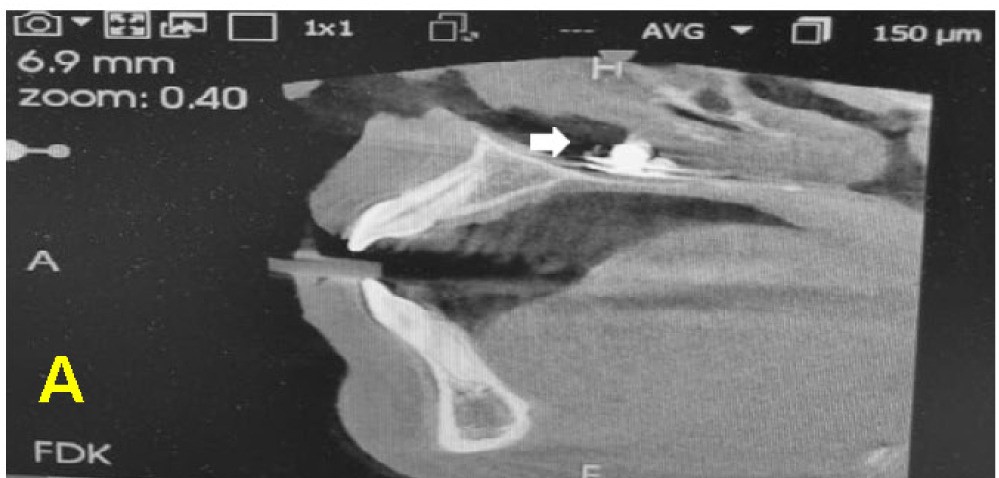

“A CBCT confirmed the presence of the foreign body with associated mild inflammation, but no significant bony damage or sinus involvement was observed.

“With informed consent from the patient’s parent, the foreign body was removed under local anaesthesia in a semi-sitting position to reduce the risk of dislodgment to the airway.”